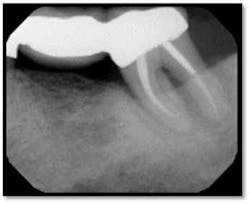

Pockets 4-9mm Class ll furcation involvement in both molars, possible endo abscess #3, (tooth is asymptomatic)

Pockets 4-7mm Possible periapical abscess #15

A full set of radiographs taken 13 months post therapy show bone fill in the deepest pockets, with generalized pocket reductions of up to 7mm.

#3 was referred for endodontic evaluation.

#’s 15 and 18 show no signs of endodontic involvement, #15 tests vital.